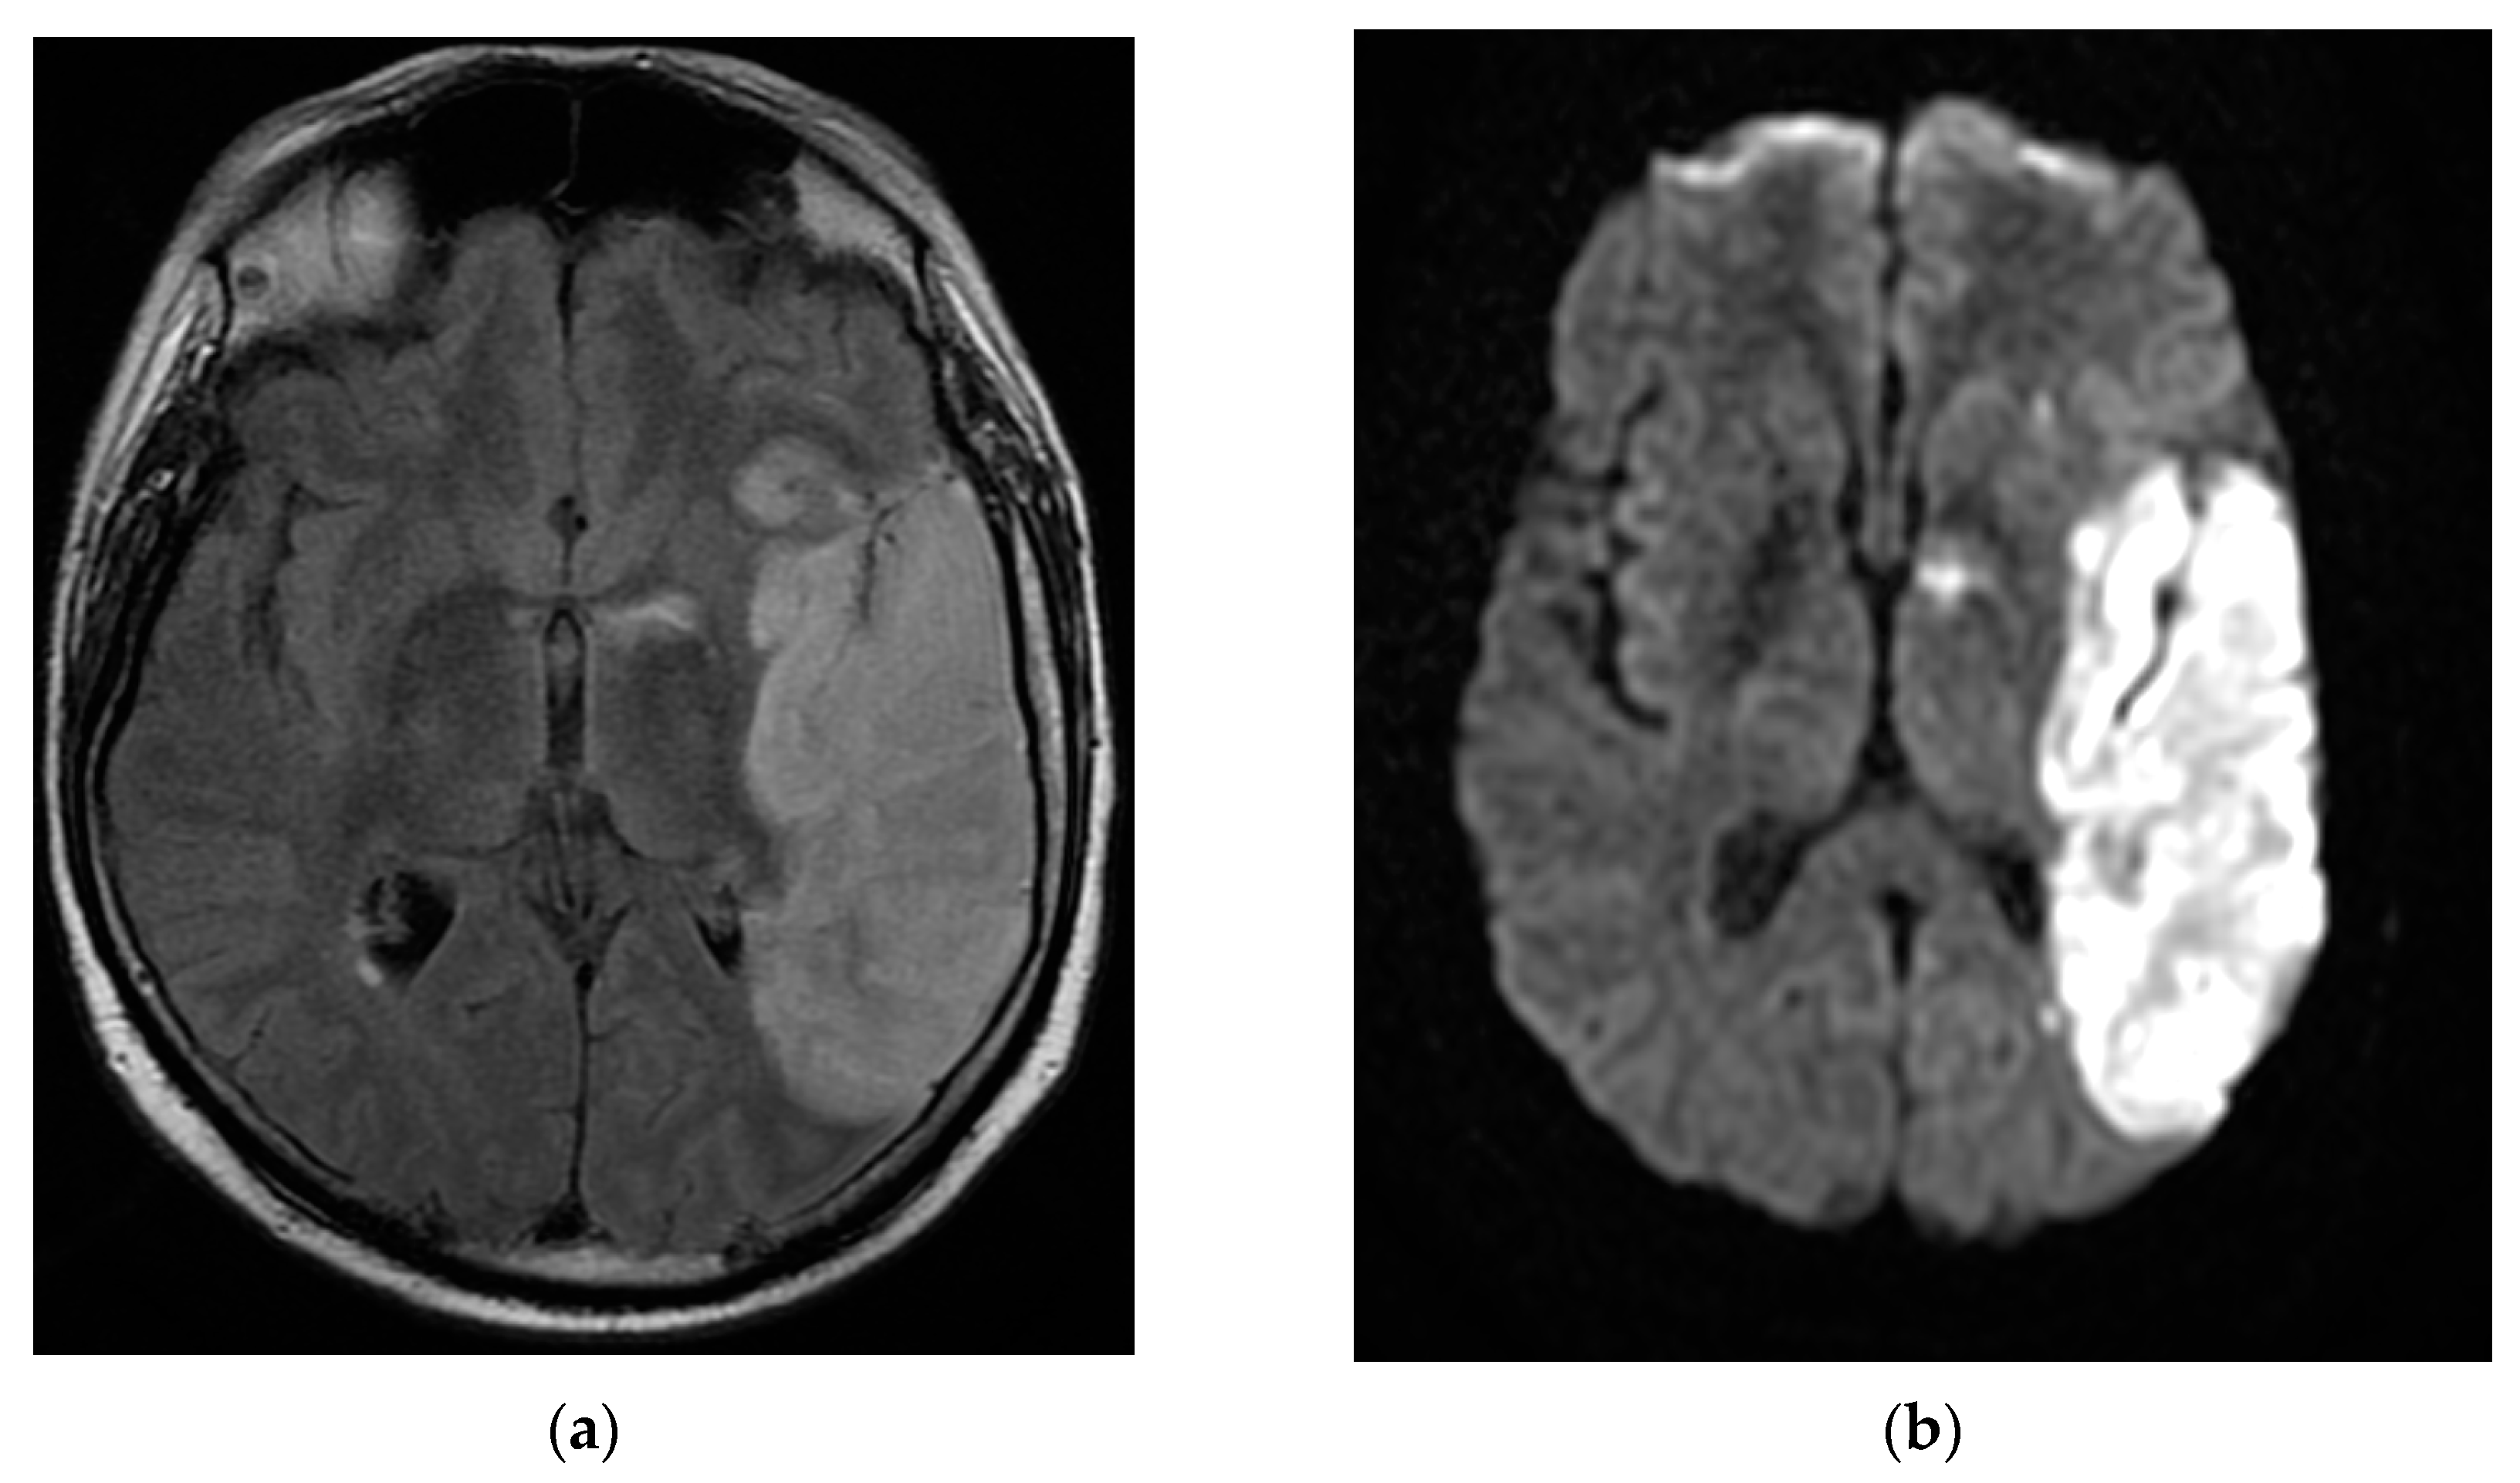

The patient returned after one month to the emergency department with right hemiparesis, mixed aphasia, incomplete left ophthalmoplegia, severe headache, and agitation, without fever. He was tested again for SARS-CoV-2 with nasal polymerase chain reaction (RT-PCR) and was found to be positive. His vitals were stable and non-contrast brain CT showed left capsulo-lenticular and temporal hypodensities. MRI brain images with and without contrast showed aspects in T2, Flair, and DWI hypersignal without contrast capture of the left temporal cortex, respectively, the hippocampal and ipsilateral parahippocampal region. An MRI brain scan also revealed multiple images in hypersignal T2, Flair, and DWI with dimensions of 2–10 mm located juxtacortically and deeply periventricular fronto-temporo-parietal bilateral. The appearance was suggestive of encephalitis (Figure 2).

Figure 2. MRI brain images with contrast showed aspects of T2 axial Flair hypersignal in the left temporal lobe (a,b), respectively, in the hippocampal and parahippocampal region (c). The lesion is hyperintense on the DWI axial image (d). MRI: magnetic resonance imaging; Flair: fluid attenuated inversion recovery; DWI: diffusion weighted imaging.